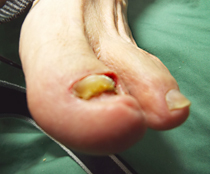

その他の症例

巻き爪、タコ、魚の目等があると症例に示すように、様々な症状を呈します。

魚の目の処置

施術前